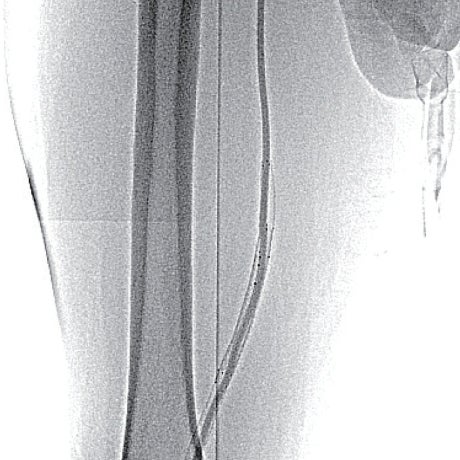

- マイクロカテーテルは硬化した閉塞部を通過せず、metal tip typeのマイクロカテーテルも通過しなかったことから、ブロッケンブロー針にて病変通過(図4)